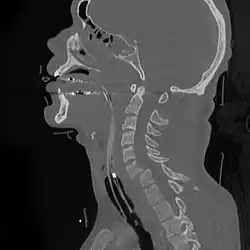

It was also previously held that X-ray of the neck should be carried out before movement of the neck was permitted. Since retention of helmet and shoulder pads would be the least disruptive to the neck as previously observed, the second question to arise became the reliability of what is referred to as cross-table lateral X-ray of the neck, the routine radiologic procedure in such cases. Although previously regarded as standard procedure, at least one study has found that football equipment is an impediment to accurate X-ray interpretation.[8] In those with significant trauma X-ray computed tomography is a more accurate test.[9]

In the event that application of the above criteria fails to indicate a 'normal cervical spine', the next step currently is CT examination, which has a reported 98-99% sensitivity for cervical spinal injury.[12] A separate imaging technique, magnetic resonance imaging, has been found to be too prone to artifacts from parts of the protective equipment to be clinically useful.[13]